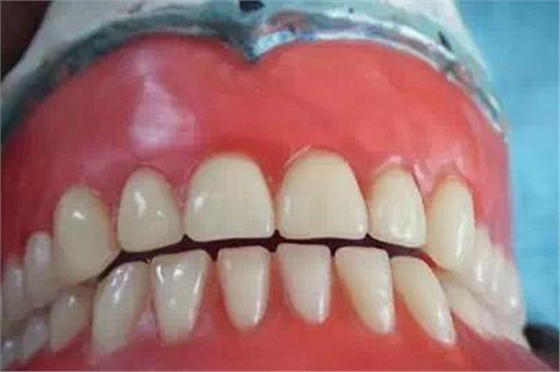

這是滬鴿公司生產(chǎn)的長(zhǎng)正中合型牙齒。

這是我用長(zhǎng)正中合型修復(fù)的全口義齒。

排牙時(shí)嚴(yán)格按照步驟進(jìn)行,咬合接觸點(diǎn)很接近書(shū)上的要求。

制作完成的義齒。